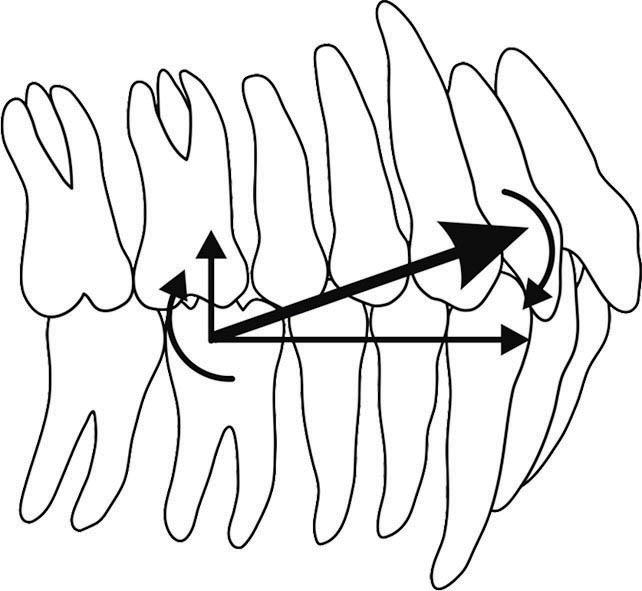

نیروی الاستیک روی دندان مولر اول باعث اکسترود شدن این دندان میشود، (البته مارجینال ریج آن با پرمولر مجاور بهم نمیخورد بلکه پلن اکلوزال میچرخد) (شکل 181-1). در زمانی که الاستیک Cl II استفاده میشود پلن اکلوزال در جهت عقربههای ساعت و در زمانی که از الاستیک Cl III استفاده میشود پلن اکلوزال خلاف جهت عقربههای ساعت میچرخد، لذا اگر بیمار کلاسII یا III متمایل به اپنبایت باشد بهتر است الاستیک را به جای دندان 6 از دندان 5 شروع کنیم تا مولفه اکسترود کننده آن تاثیر زیادی روی باز شدن بایت نگذارد. به این الاستیک نوع short میگویند (short Cl II elastic و short Cl III elastic)

شکل 181-1: چرخش پلن اکلوزال در جهت عقربههای ساعت به خاطر مصرف الاستیک کلاسII.